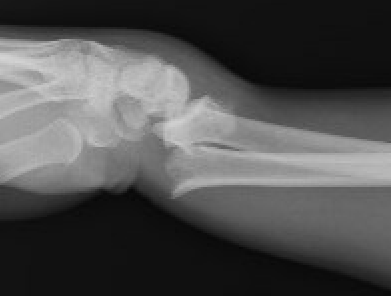

Smith's Fracture

- distal radial fracture with volar displacement

- need long arm cast in supination